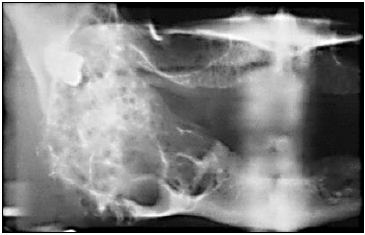

“A imagem anterior mostra uma radiografia panorâmica de uma lesão com as seguintes características: tumor com prevalência aproximadamente igual na terceira e sétima décadas de vida. Não há predileção significativa por gênero. Cerca de 80% a 85% desses tumores ocorrem na mandíbula, mais frequentemente na região de ramo e corpo de mandíbula. O tumor frequentemente é assintomático e lesões menores são detectadas somente durante o exame radiográfico. A apresentação clínica usual é de uma tumefação indolor ou expansão dos ossos gnáticos. A dor e a parestesia são incomuns, mesmo nos tumores grandes.” Qual é o nome deste tumor?